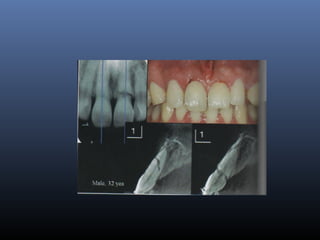

Métodos de Diagnóstico

 Visual

 Rx

EXAMEN RADIOGRAFICO

 Rx interproximales